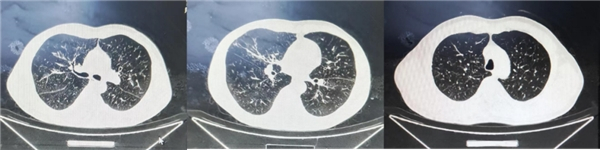

➢CT: 双肺多发小结节影及条索灶,右肺中叶散在斑片影,左肺上叶舌段实变影,考虑慢性炎性改变,结核待排。右肺、左肺上叶多发亚段支气管扩张。纵隔内多发淋巴结肿大,双肺门散在多发钙化。双肺尖胸膜增厚黏连。